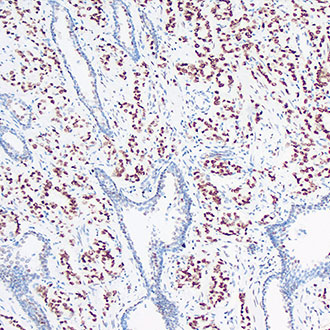

IHC

免疫组织化学(IHC)